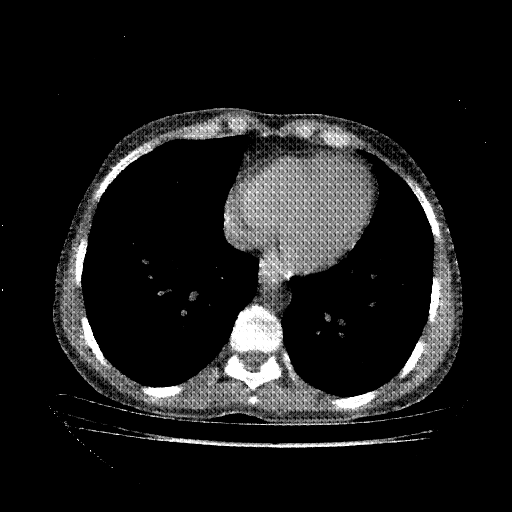

Reconstructed NATIVE CT scan (cycle consistency)

No window - Raw intensity values

Lung window (WL -600, WW 1500 β†’ Low βˆ’1350, High +150)

Mediastinum window (WL 40, WW 400 β†’ Low βˆ’160, High +240)